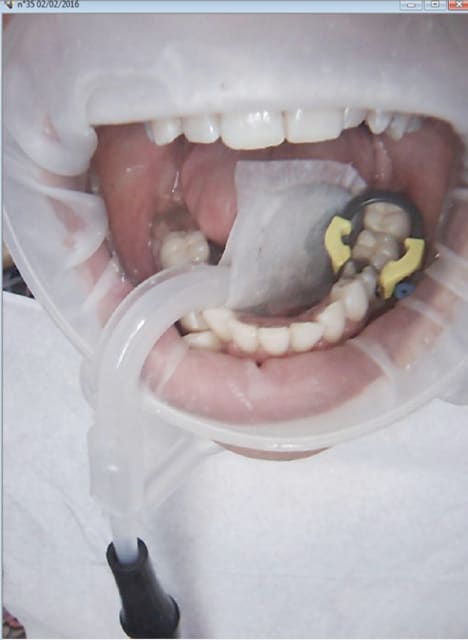

c'est magique ce truc

un peu cher mais magique

j'ai pu travailler sur un implant en place de 17 sans faire dans mon froc

j'ai pu faire des tailles sur des 17 et 27 sans avoir a choisir la langue ou la joue pour la blessure

et plein de trucs comme ça

Dans certains cas c'est magique et on se demande comment on aurait pu faire sans.

Dans d'autres ça gêne plus qu'autre chose.

C'est intéressant à avoir, mais ce n'est pas la panacée.